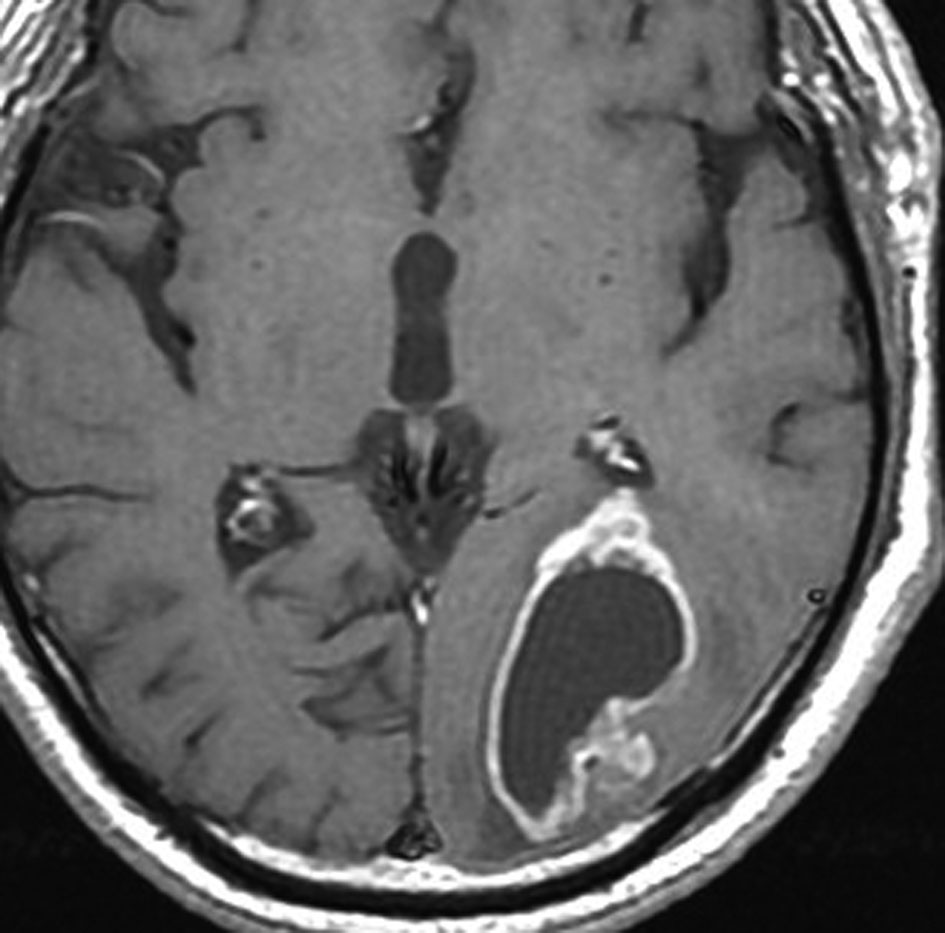

左上前頭回のびまん性グリオーマ diffuse glioma です。手術でほぼ全摘 gross total removalして54グレイの放射線治療とテモゾロマイド化学療法をしました。病理診断は,oilg 2陽性,1p/19q染色体の欠失はない退形成性乏突起星細胞腫 グレード3とされました。全体的にはグレード2であるとの病理医の意見もありましたし,当時は北大病院でもIDHの正確な分子病理診断は行われていませんでした。

5年後です。上前頭回の病巣は落ち着いていましたが,初回にはなかったはずの場所,脳梁前方に急激な再発増大を生じました。また手術で全摘出 gross total removalして,かなり絞った領域に60グレイの放射線治療とテモゾロマイド,アバスチンの投与をしました。病理診断は,IDH wild-tpye, 1p/19q non-codel, MIB 40%, ATRX positive, MGMT negativeの膠芽腫でした。

その後またしばらく寛解継続できました。

考えられることと不明なこと

- oligoとしての分化像を含むAA anaplastic astrocytomaが,再発時にGBMになったという事実があります

- これは最初から単なるGBMであったものではありません

- oligoの部分像をかなり含む,グレード3あるいは2の diffuse gliomaでしたが,1p/19qの欠失はありませんでした

- secondary GBMのように,治療反応性がよいものでしたが,再発時にはIDHはwild typeでした

- 再発は初発部位とはかなり離れた部位で,放射線線量がほとんど入っていない部位でした

- これを放射線誘発GBMとして捉えるのかどうか不明です

- 逆に,CTVはかなり広くとてあったので放射線の掛け損ないでの再発ではありません

- びまん性グリオーマが予想以上にかなり広く浸潤するということを示唆しています